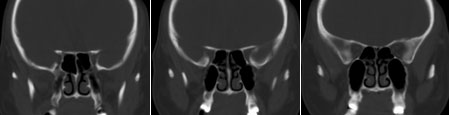

鞍区垂体窝内见一巨大类椭圆性软组织块影,前后床突受压移位、变薄,鞍底凹陷,应当能明确诊断垂体瘤。不过最好能做个mri看看视神经受累情况

蝶鞍内圆形密度不均匀,包膜完整肿块影,前床突与鞍底变薄.

意见:垂体大腺瘤.